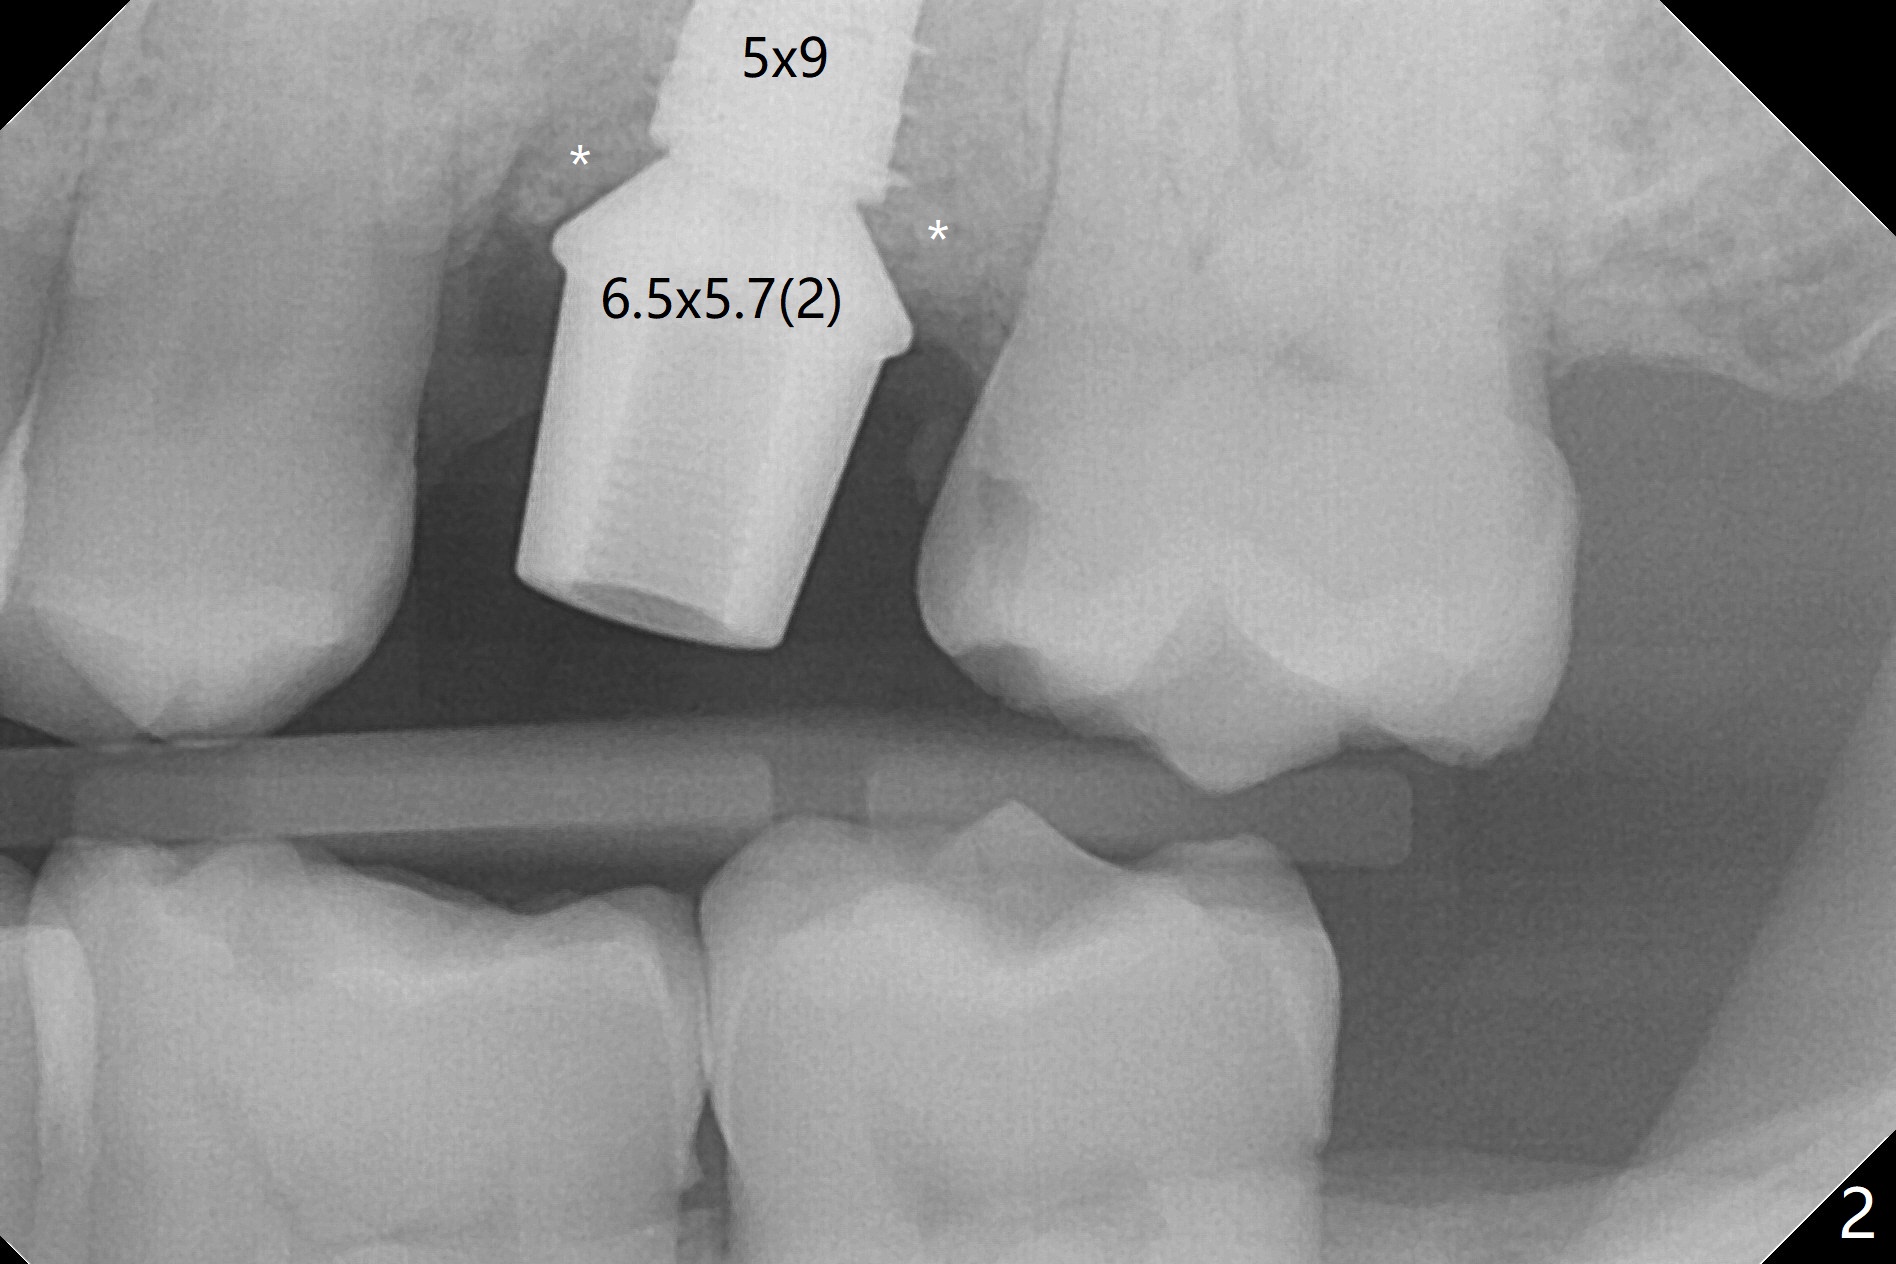

With modification of drill sequence in the last 3 steps (4.5x7.3, 4.0x8.5 and 3.5x10 mm drills) at #14 and sinus lift (Fig.1), a 5x9 mm implant is placed with ~ 50 Ncm following back up twice. Sticky bone mixed with autogenous bone (Fig.1,2 white *) is placed in the sockets before and after placement of a 6.5x5.7(2) mm abutment. Since the palatal gingival margin is recessive (Fig.3 ^), a palatal socket shield retains to prevent further recession (Fig.4 in the end of periodontal probe). Because the margin of the abutment is low, it changes to one with longer cuff (Fig.5). An immediate provisional is fabricated (Fig.6,7 P). The bone graft is indistinguishable from the original alveolus 9 months postop (Fig.8 *). The palatal socket shield is exposed 10 months postop (Fig.9 <). Since the implant is intentionally placed buccal; the sheath is not essential.